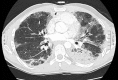

Simultaneous bilateral pneumothorax in an immunocompromised HIV patient with Pneumocystis jirovecii pneumonia

Pneumocystis in humans is caused by a unicellular and eukaryotic organism called P. jirovecii. The overall incidence of P. jirovecii pneumonia (PCP) has decreased with the use of highly active antiretroviral therapy and the use of chemoprophylaxis with trimethroprim sulfametoxazole (TMP/SMX) in cases of immunosuppressed patients. However, approximately 85% of patients with advanced HIV infections continue to experience this disease with inadequate management. Pneumocystis infection can present with spontaneous pneumothorax in 2-6% of cases [8] which can be a potentially fatal complication. We report the case of a 32-year-old man presented with P. jirovecii pneumonia who developed cystic lesions and spontaneous bilateral pneumothorax in spite of TMP/SMX treatment. We consider it an interesting clinical case because few simultaneous bilateral pneumothorax cases have been described directly related to the PCP.